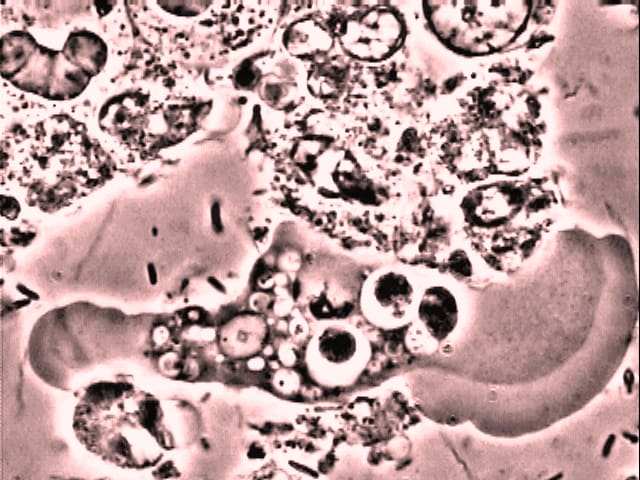

Plaque samples were prepared and examined as previously described. A drop of saturated solution of Modified Torren's Powder (Lyons 1980) was then placed at the edge of the cover slip while an area containing amoebae was kept under observation. When the solution reached the amoebae they immediately and rapidly reduced in size and became more opaque. Their internal structure could no longer be differentiated. Some amoebae floated away, suggesting that they also lost their stickiness. They showed no sign of vitality, but observation for a further twenty to thirty minutes demonstrated that the amoebae slowly expanded from these unrecognizable opaque masses to become, once again,

clearly recognizable vital amoebae.

The trial was repeated employing a skin cleanser containing Aloe Vera. This fluid not only disrupted the ability of the amoebae to adhere, but cell membrane lysis occurred in a matter of seconds. With complete disruption of the cell, the contents dispersed.